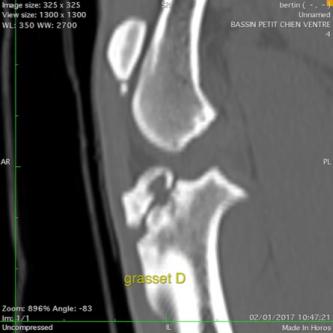

Les AUTRES SCANNER

Le scanner est utilisé dans les bilans d'extension de tumeurs mais pas que ... l'examen sert aussi à rechercher n'importe quel type de lésion dans les tissus mous et les articulations.

Masse infiltrante dans une cuisse